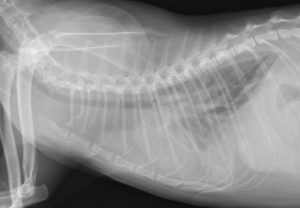

(胸水貯留時のレントゲン)

これらのデータから、ウイルスによる心筋炎を併発し、胸水はFIPそのものではなく、FIPに付随した急性の心筋炎・心不全によるものと考え、抗ウイルス薬、抗炎症剤、たまった胸水に対しては胸水の抜去を実施し、なんとか心臓の動きがもとに戻り、CPKも正常化し、胸水もまったくたまらなくなるところまでこぎつけました!